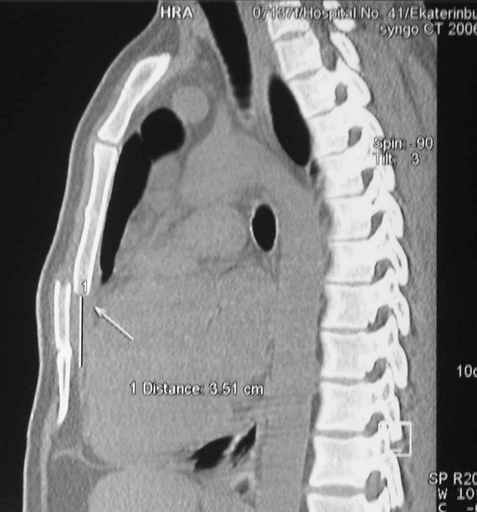

Перелом грудины

Глубокоуважаемые коллеги, Обратились за советом коллеги из соседней больницы. Мужчина 30 лет, в автоаварии ударился грудью об руль. После травмы 3 недели.

Определяется отчетдивая подвижность на месте перелома. Снимок в приложении. Пока обсуждали варианты - LCP (какую?) или спицы. Открывать зону перелома или нет? Что посоветуете?